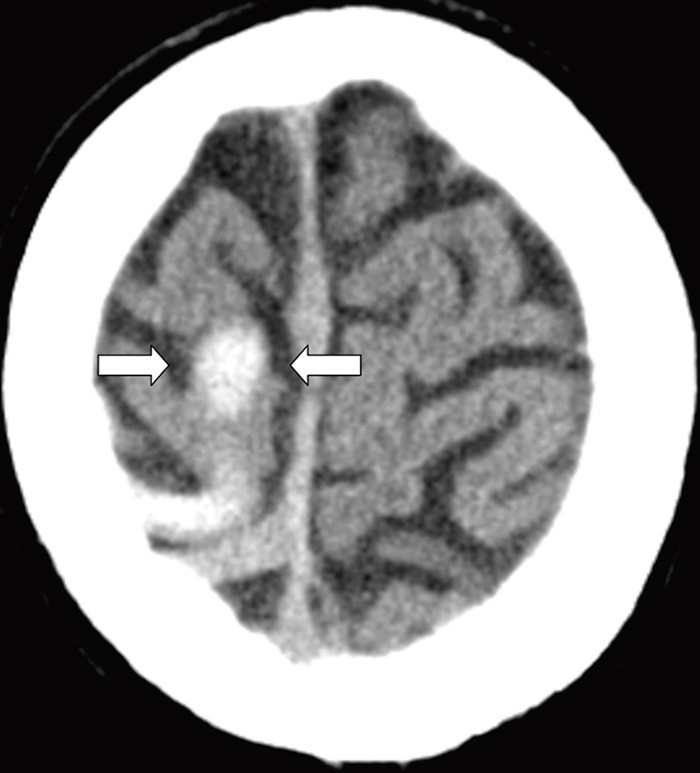

En tidligere frisk kvinne i 40-årsalderen hadde fra dagen før innleggelsen morgenhodepine og oppkast. Hun var ikke-røyker og brukte ingen medisiner eller hormoner. Innleggelsesdagen utviklet hun akutt parese i venstre ansiktshalvdel, venstresidig armparese og dysartri. Hun hadde forbigående rykninger i venstre ansiktshalvdel. Cerebral CT utført ved lokalsykehuset viste en høyattenuerende lesjon i høyre temporoparietallapp (bilde kun på nett). D-dimer var 0,8 mg/l (normalt < 0,4). Man mistenkte vaskulær hendelse i høyre hemisfære. Cerebral MR-venografi ved universitetssykehuset dagen etter viste en intraluminal venøs fyllingsdefekt svarende til høyre vena Trolard (bildet til venstre). Diffusjonsvektet cerebral MR viste en blanding av vasogent og cytotoksisk ødem temporoparietalt, typisk for venøst infarkt (bildet til høyre). Testing av forstyrrelser i trombose-koagulasjonssystemet viste aktivert protein C-resistens 0,66 (normalt 0,85 – 1,15). Pasienten fikk antikoagulasjonsbehandling og seks dager etter initiering av antikoagulasjon var ny cerebral MR-venografi normalisert. Hun ble utskrevet uten sekvele.

Cerebral venetrombose gir ofte hodepine, og kan gi nevrologiske utfall og epileptiske anfall ved samtidig infarktutvikling. Aktivert protein C-resistens disponerer for cerebral venetrombose, som er en sjelden (0,5 – 1 %) årsak til hjerneslag (1). Rask diagnostikk og behandling er vesentlig for prognosen. CT- og MR-venografi kan med høy sensitivitet og spesifisitet ikke-invasivt visualisere venøse cerebrale tromber.